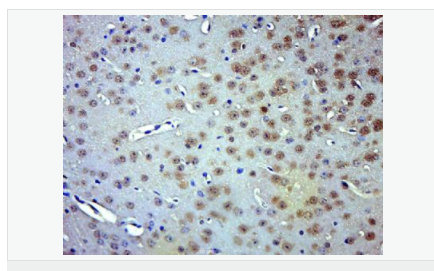

| 英文名稱(chēng) | phospho-Smad3 (Thr179) |

| 中文名稱(chēng) | 磷酸化細胞信號轉導分子SMAD3抗體 |

| 產(chǎn)品類(lèi)型 | 磷酸化抗體 |

| 研究領(lǐng)域 | 腫瘤 細胞生物 染色質(zhì)和核信號 信號轉導 干細胞 |

| 交叉反應 | Human, Mouse, Rat, (predicted: Dog, Pig, Cow, Horse, Sheep, ) |

| 產(chǎn)品應用 | WB=1:500-2000 ELISA=1:5000-10000 IHC-P=1:100-500 IHC-F=1:100-500 Flow-Cyt=1ug/Test ICC=1:100 IF=1:100-500 (石蠟切片需做抗原修復) not yet tested in other applications. optimal dilutions/concentrations should be determined by the end user. |

| 分 子 量 | 48kDa |

| 細胞定位 | 細胞核 細胞漿 |

| 免 疫 原 | KLH conjugated synthesised phosphopeptide derived from human Smad3 around the phosphorylation site of Thr179.:PE(p-T)PP |

| 產(chǎn)品介紹 | The protein encoded by this gene belongs to the SMAD, a family of proteins similar to the gene products of the Drosophila gene 'mothers against decapentaplegic' (Mad) and the C. elegans gene Sma. SMAD proteins are signal transducers and transcriptional modulators that mediate multiple signaling pathways. This protein functions as a transcriptional modulator activated by transforming growth factor-beta and is thought to play a role in the regulation of carcinogenesis. [provided by RefSeq, Apr 2009] Function: Receptor-regulated SMAD (R-SMAD) that is an intracellular signal transducer and transcriptional modulator activated by TGF-beta (transforming growth factor) and activin type 1 receptor kinases. Binds the TRE element in the promoter region of many genes that are regulated by TGF-beta and, on formation of the SMAD3/SMAD4 complex, activates transcription. Also can form a SMAD3/SMAD4/JUN/FOS complex at the AP-1/SMAD site to regulate TGF-beta-mediated transcription. Has an inhibitory effect on wound healing probably by modulating both growth and migration of primary keratinocytes and by altering the TGF-mediated chemotaxis of monocytes. This effect on wound healing appears to be hormone-sensitive. Regulator of chondrogenesis and osteogenesis and inhibits early healing of bone fractures. Positively regulates PDPK1 kinase activity by stimulating its dissociation from the 14-3-3 protein YWHAQ which acts as a negative regulator. Subcellular Location: Cytoplasm. Nucleus. Cytoplasmic and nuclear in the absence of TGF-beta. On TGF-beta stimulation, migrates to the nucleus when complexed with SMAD4. Through the action of the phosphatase PPM1A, released from the SMAD2/SMAD4 complex, and exported out of the nucleus by interaction with RANBP1. Co-localizes with LEMD3 at the nucleus inner membrane. MAPK-mediated phosphorylation appears to have no effect on nuclear import. PDPK1 prevents its nuclear translocation in response to TGF-beta. Post-translational modifications: Phosphorylated on serine and threonine residues. Enhanced phosphorylation in the linker region on Thr-179, Ser-204 and Ser-208 on EGF and TGF-beta treatment. Ser-208 is the main site of MAPK-mediated phosphorylation. CDK-mediated phosphorylation occurs in a cell-cycle dependent manner and inhibits both the transcriptional activity and antiproliferative functions of SMAD3. This phosphorylation is inhibited by flavopiridol. Maximum phosphorylation at the G(1)/S junction. Also phosphorylated on serine residues in the C-terminal SXS motif by TGFBR1 and ACVR1. TGFBR1-mediated phosphorylation at these C-terminal sites is required for interaction with SMAD4, nuclear location and transactivational activity, and appears to be a prerequisite for the TGF-beta mediated phosphorylation in the linker region. Dephosphorylated in the C-terminal SXS motif by PPM1A. This dephosphorylation disrupts the interaction with SMAD4, promotes nuclear export and terminates TGF-beta-mediated signaling. Phosphorylation at Ser-418 by CSNK1G2/CK1 promotes ligand-dependent ubiquitination and subsequent proteasome degradation, thus inhibiting SMAD3-mediated TGF-beta responses. Phosphorylated by PDPK1. Acetylation in the nucleus by EP300 in the MH2 domain regulates positively its transcriptional activity and is enhanced by TGF-beta. Ubiquitinated. Monoubiquitinated, leading to prevent DNA-binding. Deubiquitination by USP15 alleviates inhibition and promotes activation of TGF-beta target genes. Poly-ADP-ribosylated by PARP1 and PARP2. ADP-ribosylation negatively regulates SMAD3 transcriptional responses during the course of TGF-beta signaling. DISEASE: Colorectal cancer Loeys-Dietz syndrome 3 Similarity: Belongs to the dwarfin/SMAD family. Contains 1 MH1 (MAD homology 1) domain. Contains 1 MH2 (MAD homology 2) domain. SWISS: P84022 Gene ID: 4088 Database links: Entrez Gene: 4088 Human Entrez Gene: 17127 Mouse Omim: 603109 Human SwissProt: P84022 Human SwissProt: Q8BUN5 Mouse Unigene: 727986 Human Unigene: 742270 Human Unigene: 7320 Mouse Unigene: 10636 Rat Important Note: This product as supplied is intended for research use only, not for use in human, therapeutic or diagnostic applications. |